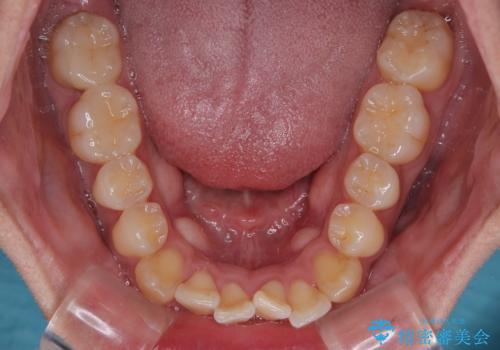

- 前歯の反対咬合などを気にして来院された患者様です。

ワイヤー矯正、マウスピース矯正どちらでも対応可能であったので、ご本人の希望によりインビザラインにて矯正治療を行うこととしました。

毎日の装着時間をしっかりと守ってくださり、1年強の短期間で、あっという間に治療を終えることができました。